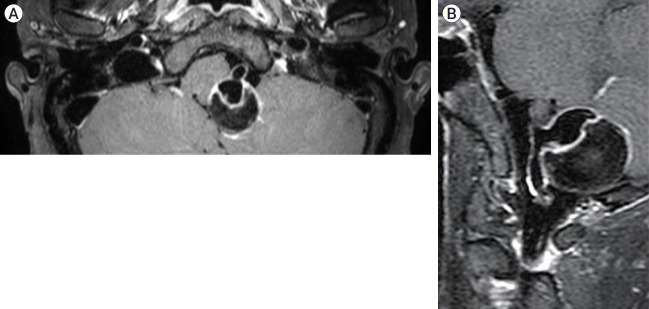

纤维肌发育不良(FMD)是一种主要影响女性的非炎症性动脉疾病。多项研究表明,在经历颈动脉或椎动脉夹层(VAD)的患者中,FMD的患病率增加。本病例报告介绍了一名57岁的女性,她表现出头痛,并被诊断为部分血栓形成的椎动脉巨大动脉瘤。该动脉瘤用分流器和线圈成功治疗,但两周后发现新发的椎动脉破裂,导致内陷。本病例报告强调了对疑似FMD患者的夹层和动脉瘤治疗的认识和理解的必要性。

Fibromuscular dysplasia (FMD) is a noninflammatory arterial diseases that affects predominantly women. Multiple studies have demonstrated an increased prevalence of FMD in patients who experience carotid or vertebral artery dissection (VAD). This case report presents a 57-year-old female who presented with a headache and was diagnosed with partially thrombosed giant aneurysm of vertebral artery. This aneurysm was successfully treated with flow-diverter and coil, but new onset rupture of vertebral artery was detected two weeks later, leading to internal trapping. This case report underscores the need for awareness and understanding of treatment of dissection and aneurysm in patient who is suspected FMD.